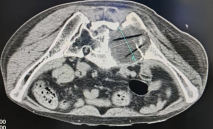

本次手术采用CT引导下经皮穿刺的微创方式,全程在精准影像定位下进行,最大程度保障安全与精准。

术中,医生通过CT清晰锁定病灶位置,先精准留取病理标本,为后续治疗提供依据,同时精准规划冷冻消融的范围。考虑到患者瘤体巨大,无法一次性彻底处理,本次手术重点针对左侧臀部瘤体,首要目标是解除其对血管、神经的压迫,缓解患者的核心痛苦。

手术过程顺利。术后即刻CT扫描清晰显示:冷冻形成的冰球完美包裹整个肿瘤病灶,消融范围精准、到位,无遗漏、无损伤。